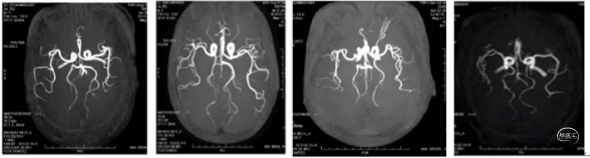

A、基底动脉大脑后动脉 B、右侧胚胎型大脑后动脉 C、左侧胚胎型大脑后动脉D、双侧胚胎型大脑后动脉。

DWI显示双侧丘脑穿支动脉梗塞。MRI显示基底动脉纤细,远端无大脑后动脉,双侧大脑后动脉通过颈内动脉供血,因为无血管出路,基底动脉纤细。